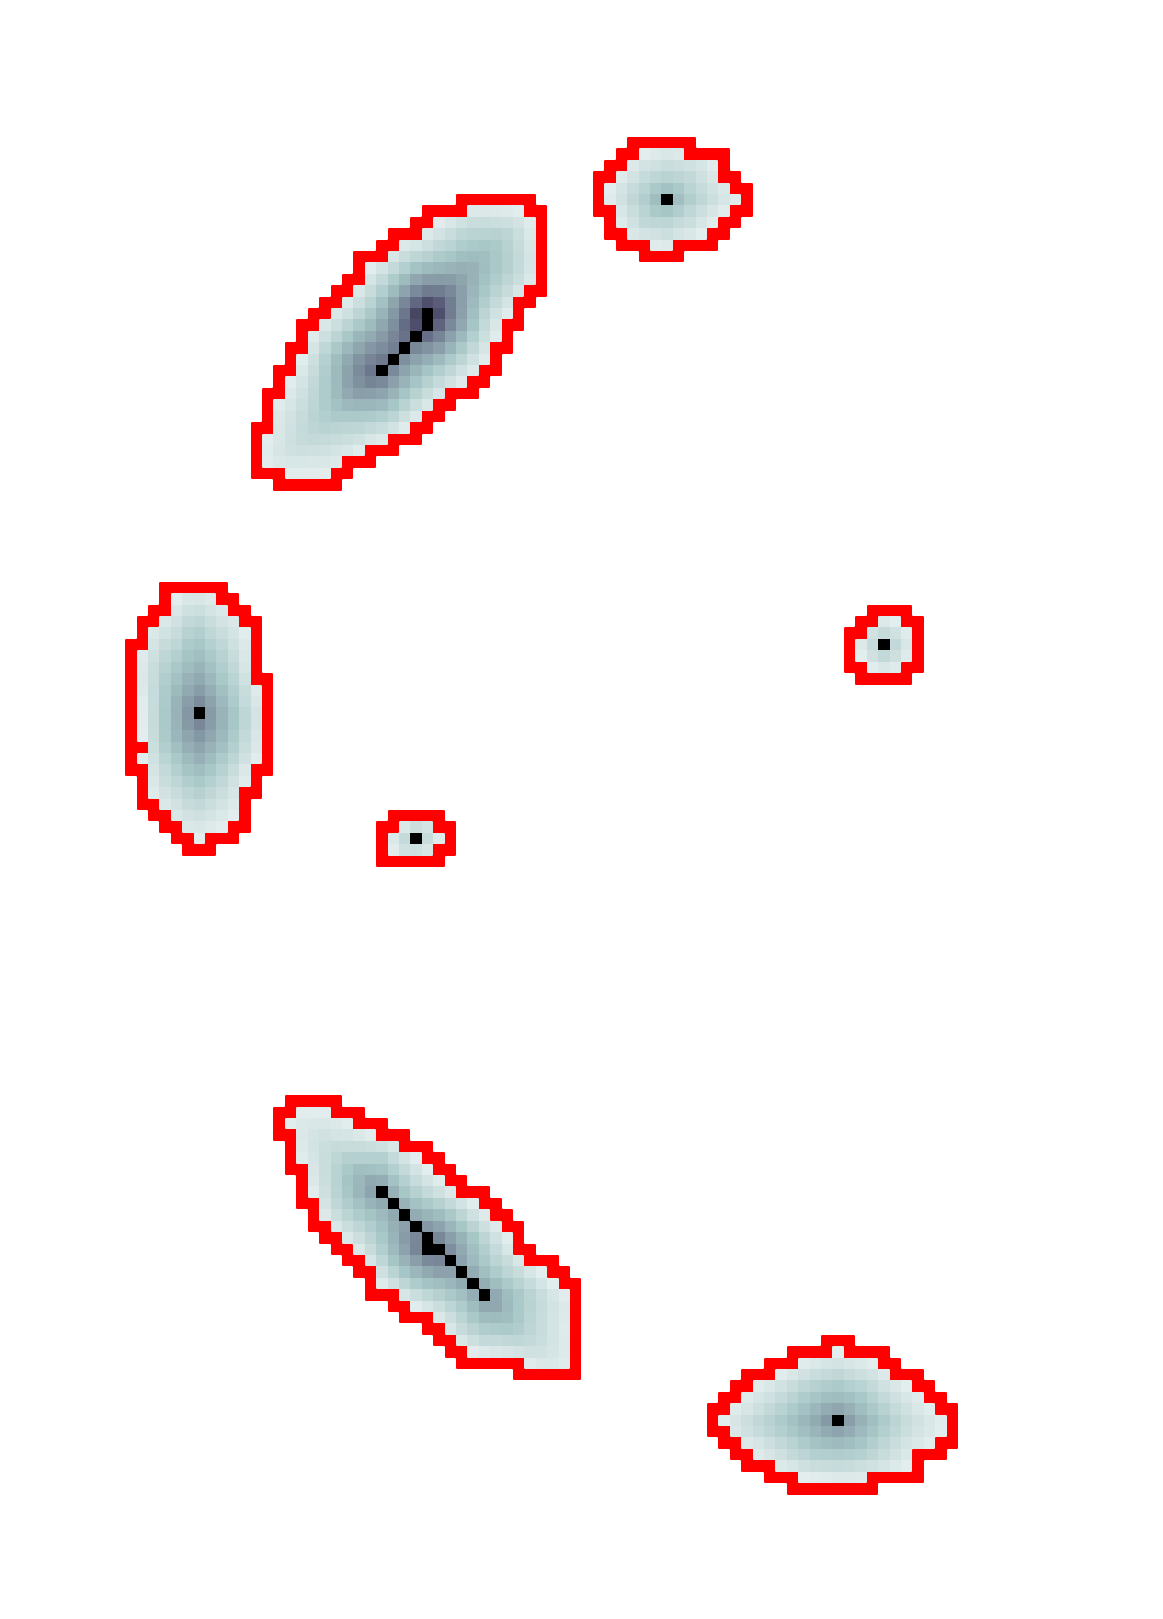

The scalar vesselness responses of both HCP and PC images are determined using the state-of-the-art Frangi filter (FFR) [8], and Optimally Oriented Flux (OOF) [12]. Also, the connected vesselness map (CVM) and the associated tensor field (TF) are synthesized for the same dataset using VTrails. The connectedness of the considered scalar maps is qualitatively assessed and the TF is inspected as proof of concept in section 3.1.

3.1 Connectedness of the Vesselness Map

Fig. 3 shows the connectedness of vessels recovered from state-of-the-art vascular enhancers and curvilinear ridge detectors FFR and OOF together with the proposed CVM for the synthetic HCP and the real PC images.

On the synthetic phantom, FFR shows a fragmented and rough vesselness response in correspondence of irregularly shaped sections of the structure. Also, the response at the bifurcation is not smoothly connected with the branches (triangular loop). Conversely, OOF recovers the phantom connectedness at the branch-point, and the vesselness response is consistent along the tortuous curvilinear section, however ghosting artifacts are observed as the shape of the phantom becomes irregular (C-like) or differs from a cylindrical tube. Also, close convoluted structures, which change scale rapidly in the HCP, produce inconsistent responses of OOF (fig. 3). CVM shows here a strongly connected vesselness response in correspondence of both regular and irregular tubular sections, with local maxima at structures’ mid-line. The connectedness of the structures is emphasized regardless the complexity of the shape, and it resolves spatially the tortuous curvilinear ‘kissing vessels’ without additional ghosting artifacts, despite the smooth profile.

Similar results are observed on the PC dataset: FFR has a poor connected response in the noisy and low-resolution image. Vessels are overall enhanced, however thin and fragmented structures remain disconnected. Overall, the vesselness response is not uniform within the noisy structures, where maximal values are often off-centred. A more consistent response is obtained from OOF, where the connectedness of vessels is improved. Maximal response is observed at the mid-line of vessels, however, noise rejection is poor. CVM strongly enhances here the vessel connectivity. The fragmented vessels of PC have a continuous and smooth response in CVM with higher values and a more defined profile. Large vessels shows solid connected regions with local maxima at mid-line as in OOF. Conversely from OOF, CVM shows improved noise rejection in the background.

The respective tensor fields (TF) synthesized on both HCP and PC show consistent features. The TF’s characteristics are in line with the connectedness of CVM: enhanced and connected vessels are associated with high anisotropy, whereas background areas show a predominant isotropic component.